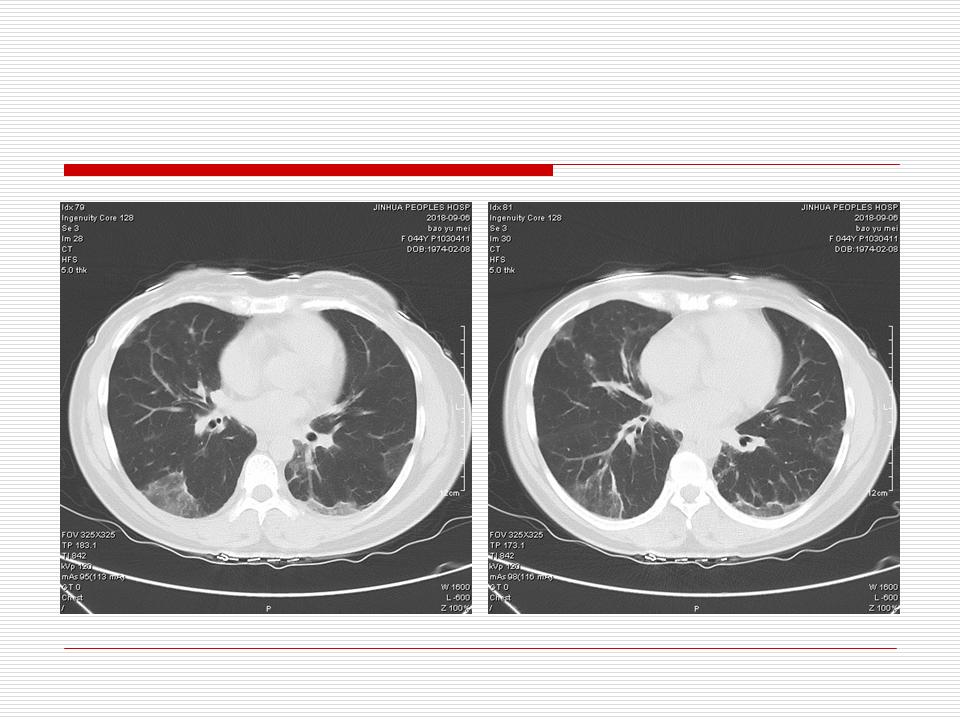

肺部阴影永恒且最重需要鉴别的是:到底是炎症还是肿瘤?但临床的病例中的影像表现难以界定或有些肿瘤特征,同时又有些炎症特点是非常常见的情况。作为临床医生我们怎么去总结分析,并找到之所以是炎症或之所以是肿瘤的细微差别或特点非常重要,也非常有用。2019.12.7浙江省2019年胸心外科学学术年会在宁波召开时,我的临床病例分析与经验总结<那些像肺癌的炎症与像炎症的肺癌>获得在大会交流的机会,以下为该PPT的内容,与你分享,希望对同道有益,有借鉴与启迪。若有探讨与进一不完善的建议,欢迎文末留言讨论: